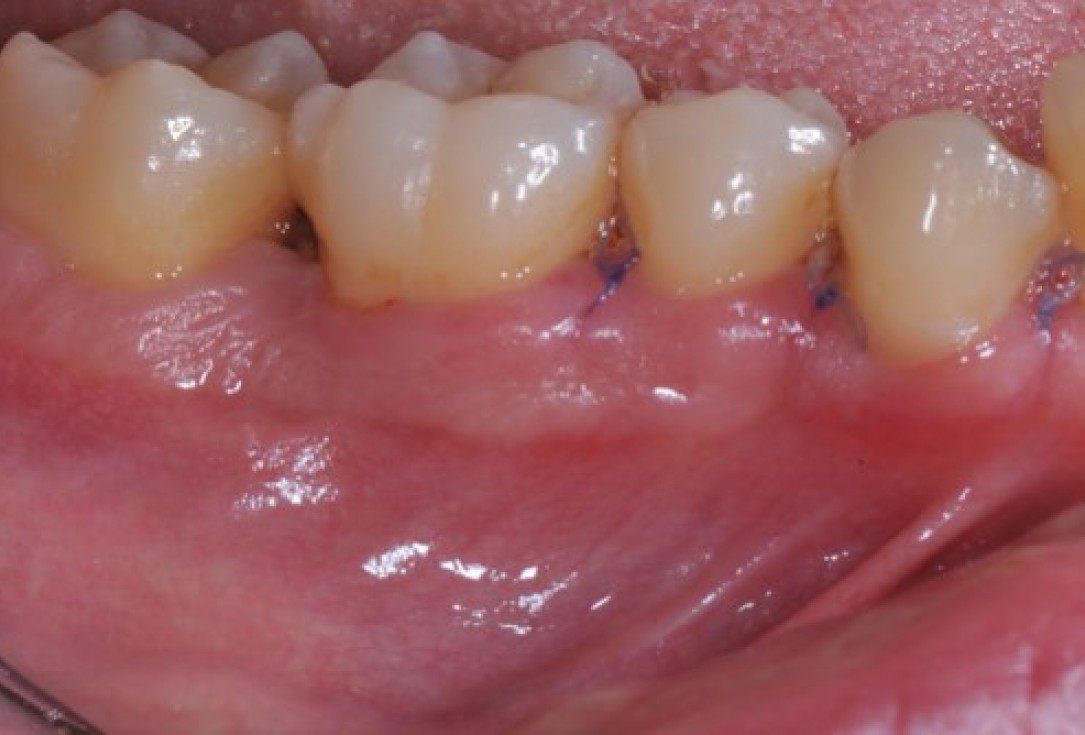

Radiographic view before periodontal regenerative therapy with Straumann® Emdogain®. A deep intrabony defect appeared mesially and distally on the left mandibular first premolar. Pre-surgical probing measured 8 mm. The defect morphology presented as well-contained.